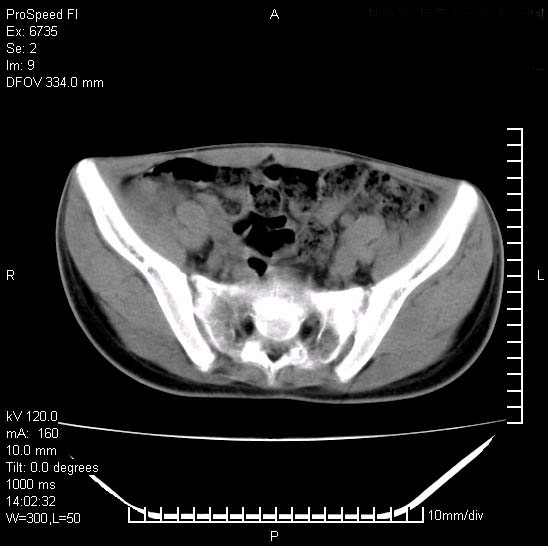

患者自诉胯部疼痛两年余,在当地服用中药,半月前至本院考虑骶髂关节结核,给予抗痨治疗。现发展至右下肢疼痛明显,活动受限,以膝关节处明显,拍膝关节平片无明显异常。

两侧骶骼关节改变,考虑强直性脊炎

左侧骶髂关节面限局性骨破坏,边缘硬化关节腔见钙化物;不出外tb

右侧骶髂关节也有类似改变,只是较左侧轻,首先考虑强直性脊柱炎,不除外结核,建议作hla-b27检查。

典型强脊炎改变,髋关节亦有累及

符合强直性脊柱炎表现。